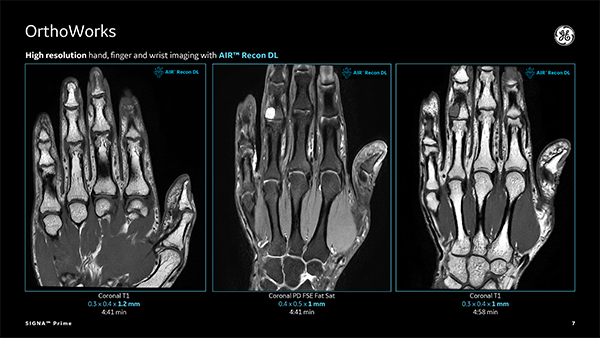

よりシャープに,くっきりと。GEが長年深めてきたMR画像に対する知見を余すところなくSIGNA™ Primeに注ぎ込みました。SIGNA™ Primeは最先端のTotal Digital Imaging(TDI)テクノロジーを搭載。さらに,GE独自のディープラーニングベースで開発された画像再構成アルゴリズムであるAIR™ Recon DLが,先生方の日々の診断を強力にサポートします。画像のノイズ除去だけではなく,SNRと画像の尖鋭度が向上した高画質を実現しながら,スキャン時間を大幅に短縮しています。